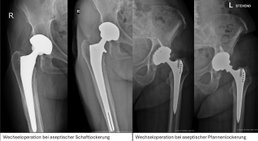

Revisionsoperationen Hüfte

Schmerzen nach einer Hüfttotalprothese können mannigfaltige Ursachen haben. Weichteilprobleme, „Abnutzungserscheinungen“ älterer Prothesensysteme, Lockerungen oder Keimbesiedelungen des Implantates (Infektion) sind mögliche Gründe. Die Diagnostik beinhaltet...